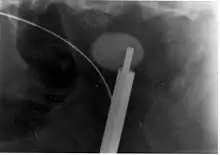

تفتيت الحصى

تفتيت الحصاة بموجات صادمة من خارج الجسم هي تقنية غير تَوَغُلية لإزالة حصى الكلى. ويتم استخدامها غالبا عندما تكون الحصوة موجودة بالقرب من حويضة الكلية. حيث يتم استخدام آلة تفتيت الحصاة لإرسال نبضات عالية الكثافة ومركزة من الموجات فوق الصوتية، تعمل على تجزئة الحصى على مدى حوالي 30-60 دقيقة. بعد إدخاله في الولايات المتحدة في فبراير 1984، تم قبول تلك التقنية على نطاق واسع كبديل لعلاج حصى الكلى والحالب.[88] ويستخدم حاليًا في علاج الحصوات غير المعقدة، التي تقع في الكلى والجزء العلوي من الحالب، شريطة أن يكون حجم حصوة الكلى أقل من 20 مم، وتركيب الكلى المعنية طبيعي.[89][90] بينما في الحصوات التي يكون حجمها أكبر من 10 مم، قد لا يساعد تفتيت الحصوات بموجات صادمة من الخارج على تفتيت الحصوات في جلسة واحدة. بدلًا من ذلك، قد تكون هناك حاجة لاثنين أو ثلاثة. ويمكن علاج حوالي 80- 85٪ من الحصوات الكلوية البسيطة بشكل فعال باستخدام آلة تفتيت الحصوات.[3] وهناك عدد من العوامل التي يمكن أن تؤثر على فعاليتها، بما في ذلك التركيب الكيميائي للحصوة، والتشريح الكلوي الشاذ، وموقع الحصوات داخل الكلى، ووجود موه الكلية، ومؤشر كتلة الجسم، والمسافة بين الحصوة وسطح الجلد.[88] وتتضمن الآثار الجانبية الشائعة لتفتيت الحصوات باستخدام الموجات فوق الصوتية: الصدمة الحادة، مثل كدمات في موقع تطبيق الموجات الصادمة، والأضرار التي تلحق بالأوعية الدموية في الكلى.[91][92] في الواقع، فإن الغالبية العظمى من الناس الذين يعالجون بجرعة قياسية من موجات الصدمة باستخدام إعدادات العلاج المقبولة حاليًا من المرجح أن تواجه درجة ما من القصور الكلوي الحاد.[88] ويعتمد القصور الكلوي الحاد الناجم عن تفتيت الحصوات بالموجات الصادمة على الجرعة (يزيد مع العدد الإجمالي لموجات الصدمة التي تُعطى، ومع إعدادات الطاقة من آلة التفتيت)، ومن الممكن أن القصور شديد،[88] ويتضمن نزيف داخلي، وأورام دموية تحت المحفظة. في حالات نادرة، قد تتطلب مثل هذه الحالات نقل دم، وقد تؤدي إلى الفشل الكلوي الحاد. قد ترتبط معدلات الورم الدموي بنوع آلة التفتيت المستخدمة. وتم الإبلاغ عن معدلات حدوث ورم دموي بنسبة أقل من 1٪، وقد تصل إلى 13٪ لآلات تفتيت الحصى المختلفة.[92] وتُظهِر الدراسات الحديثة انخفاض إصابة الأنسجة الحاد عندما يتضمن بروتوكول العلاج وقفة قصيرة بعد بدء العلاج، مما يعمل على تحسين التفتيت الحصوي، وانخفاض الإصابة عند تطبيق تقنية تفتيت الحصوات باستخدام موجات الصدمة بمعدل بطيء.[88]